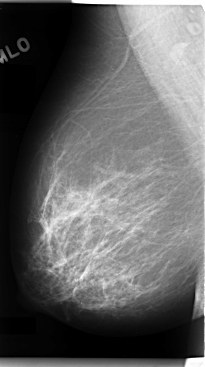

C_0089_1.RIGHT_MLO

RIGHT_MLO LINES 4768 PIXELS_PER_LINE 2656 BITS_PER_PIXEL 12 RESOLUTION 50 NON_OVERLAY